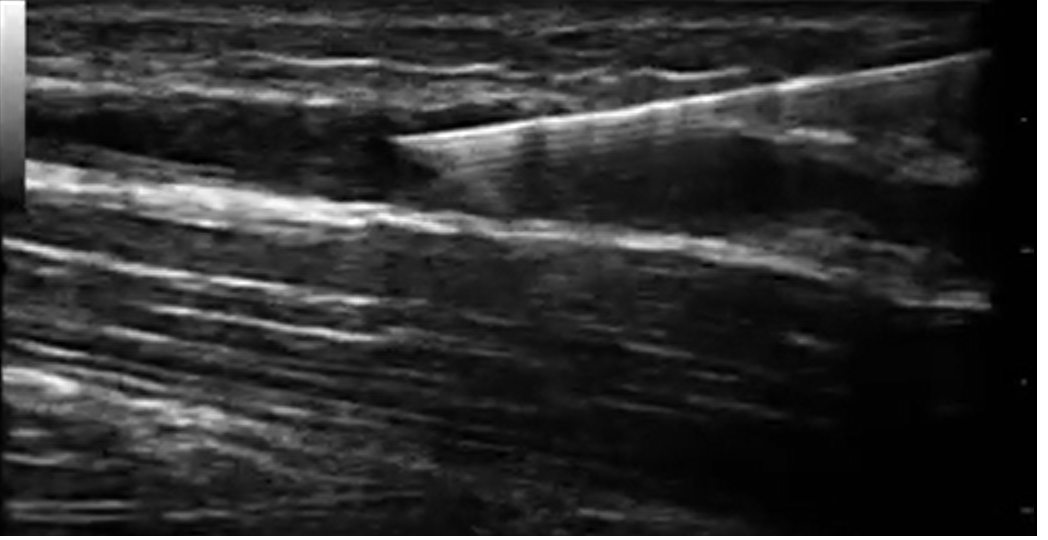

ECOGRAFÍA DUPLEX VENOSO

El estudio Duplex nos permite diagnosticar de manera rápida y certera problemas venosos. En Franco Vascular cuenta con la tecnología y la confianza de ser realizado por un médico subespecialista. Un buen tratamiento comienza con un buen diagnóstico.

ESTUDIOS ECOGRAFÍA DOPPLER/DUPLEX

Realizamos ecografía Doppler arterial de miembros inferiores o superiores, Doppler de arterias renales, carotídeo, esplenoportal, arterias temporales, aorta abdominal entre otros. Si necesita un estudio Duplex/Doppler consulte con nosotros.

DOPPLER VENOSO MEDELLIN

Contamos con equipos de alta tecnología y ultra-alta definición que nos permiten diagnosticar problemas circulatorios.